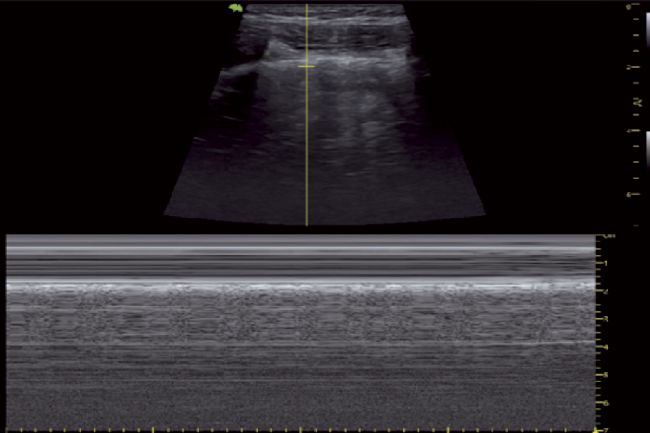

正常肺超聲M型圖像(沙灘樣征)